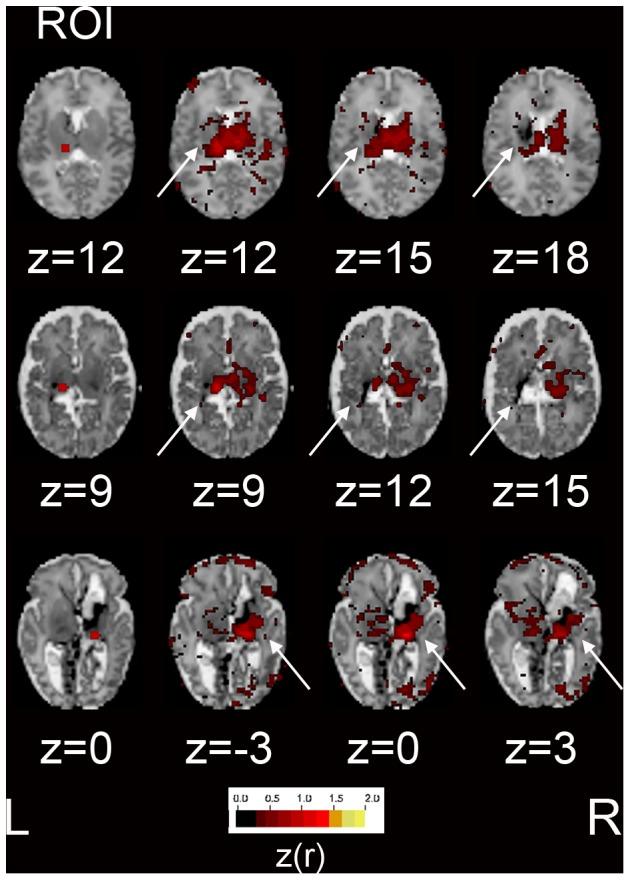

The cerebral white matter is vulnerable to injury in very preterm infants (born prior to 30 weeks gestation), resulting in a spectrum of lesions. These range from severe forms, including cystic periventricular leukomalacia and periventricular hemorrhagic infarction, to minor focal punctate lesions. Moderate to severe white matter injury in preterm infants has been shown to predict later neurodevelopmental disability, although outcomes can vary widely in infants with qualitatively comparable lesions. Resting state functional connectivity magnetic resonance imaging has been increasingly utilized in neurodevelopmental investigations and may provide complementary information regarding the impact of white matter injury on the developing brain. We performed resting state functional connectivity magnetic resonance imaging at term equivalent postmenstrual age in fourteen preterm infants with moderate to severe white matter injury secondary to periventricular hemorrhagic infarction. In these subjects, resting state networks were identifiable throughout the brain. Patterns of aberrant functional connectivity were observed and depended upon injury severity. Comparisons were performed against data obtained from prematurely-born infants with mild white matter injury and healthy, term-born infants and demonstrated group differences. These results reveal structural-functional correlates of preterm white matter injury and carry implications for future investigations of neurodevelopmental disability.